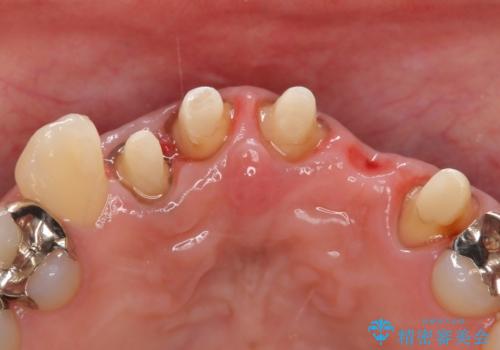

- 昔入れた被せ物と歯茎の間の隙間が気になると来院された方の症例です。

右上1、2番目の歯と左上1、2、3、番目の歯のブリッジを除去し、オールセラミッククラウンによる補綴を行うことで見た目を改善しました。